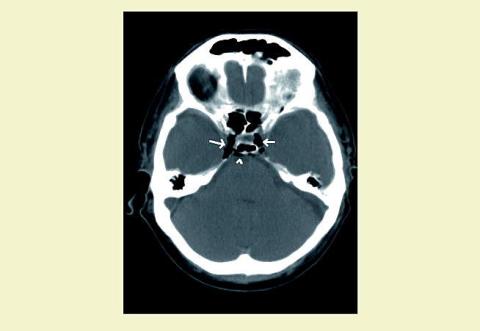

En 48-årig mand, der havde hovedtraume, blev indlagt på hospitalet. Computertomografier (CT) viste subdurale hæmatomer, subaraknoidalblødning og bilaterale frontale kontusionsinfarkter med blødning. På fjerdedagen fik patienten hjertestop, og en CT viste nytilkommen luft i begge sinus cavernosus (pile) og i veneplekserne bag clivus (pilehoved) samt ophævet diskriminering mellem grå og hvid substans. På thoraxbilledet sås det centrale venekateter (CVK) med spidsen i højre atrium. En efterfølgende firkarsangiografi viste ophævet cerebralt flow, og patienten var dermed hjernedød.

Luft i de intrakraniale vener ses efter hjertestop, hvor der har været foretaget usuccesfuld genoplivning [1]. Luften kommer utilsigtet fra et CVK og løber retrogradt i venerne, og dette retrograde flow tilskrives hjertemassagen, hvor der sker samtidig kompression af alle fire hjertekamre og de centrale vener. Luften samler sig i de venøse sinus i fossa posterior og sinus cavernosus og transporteres ikke væk på grund af den ophævede cerebrale cirkulation. Luft i venerne er tegn på en dårlig prognose.